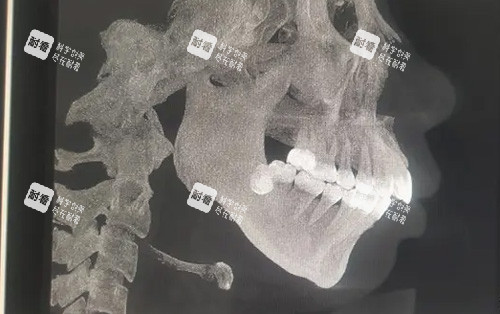

术前精细建模:通过CT扫描和3D数字建模,提前模拟手术路径,避免神经损伤;

“去年有个患者从深圳赶来,她之前在别的医院做正颌失败,导致咬合紊乱。”艾伟健团队接诊后,用3D导航技术重新设计手术方案,术后不仅脸型改善,咀嚼功能也改善正常。“这种修复类手术,对医生技术和设备要求极高,普通机构根本接不了。”